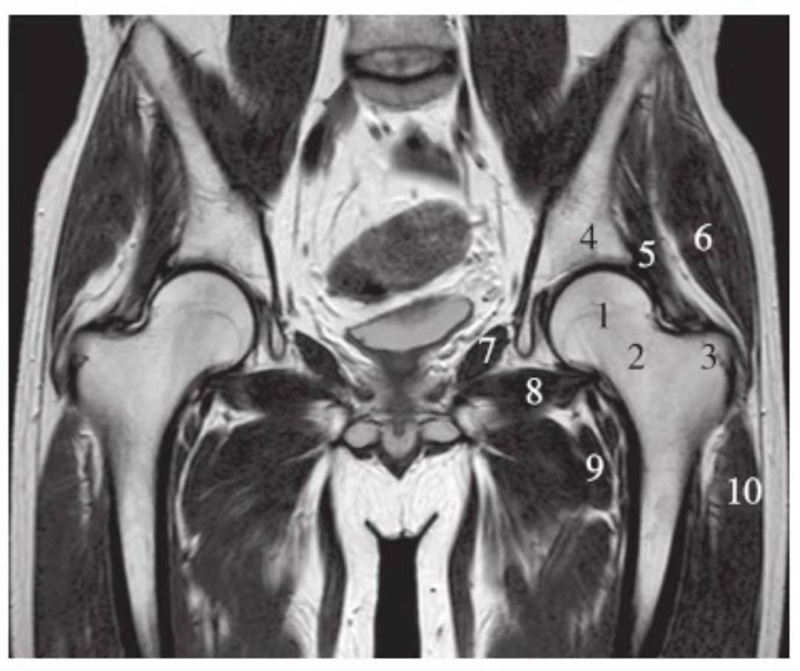

冠状位

正常髋关节经股骨头前缘层面T1WI像

1.股骨头;2.耻骨;3.髂骨;4.髂腰肌;5.内收肌群;6.臀小肌;7.臀中肌;8.关节囊及髂股韧带